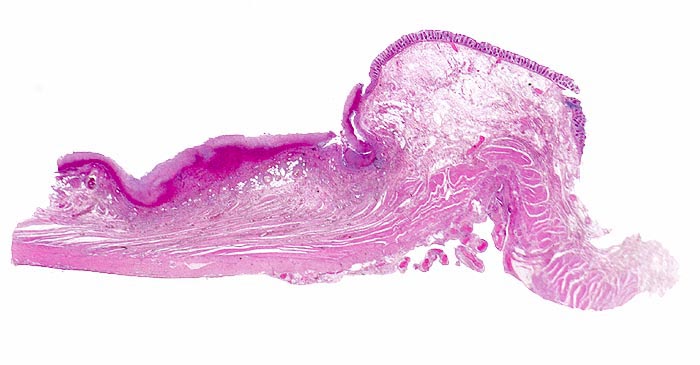

Morphologische Merkmale:

• Herdförmige Schleimhautnekrosen.

• In den Nekrosezonen pilzförmige Pseudomembranen bestehend aus nekrotischem Detritus, Entzündungszellen und Fibrin.

• Zwischen den Pseudomembranen normale Kolonschleimhaut. Das sollte der Kliniker dem Pathologen mitteilen: